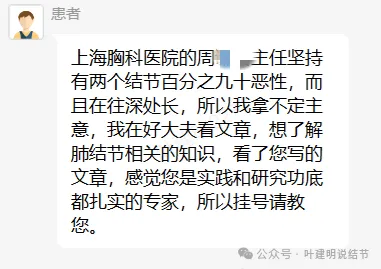

上海胸科医院周姓主任坚持两个结节百分之九十恶性,而且在往深处长。